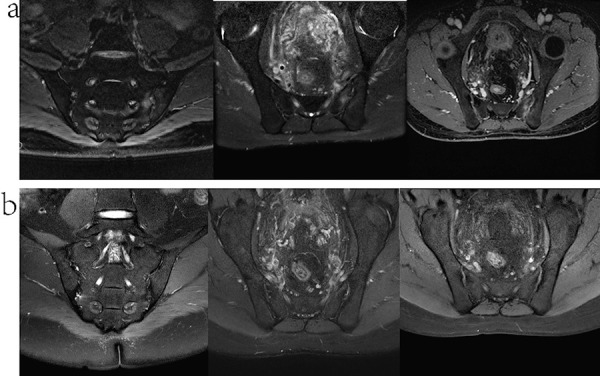

Case report: Here, we report the successful treatment of AS with secukinumab in a 36-year-old male patient undergoing hemodialysis. The patient presented with recurrent lumbosacral pain and tested positive for HLA-B27. After treatment, significant improvements were observed in both the imaging characteristics of the synovial joints and the patient's symptoms.